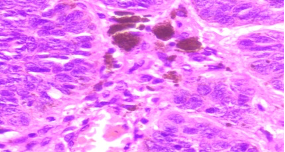

HISTOPATHOLOGY

Fig shows an endoscopic biopsy from a 54 year old individual. Identify the anatomical part of the intestine. What is the pathology. With what clinical symptoms do these patients present? (see surface epithelium)